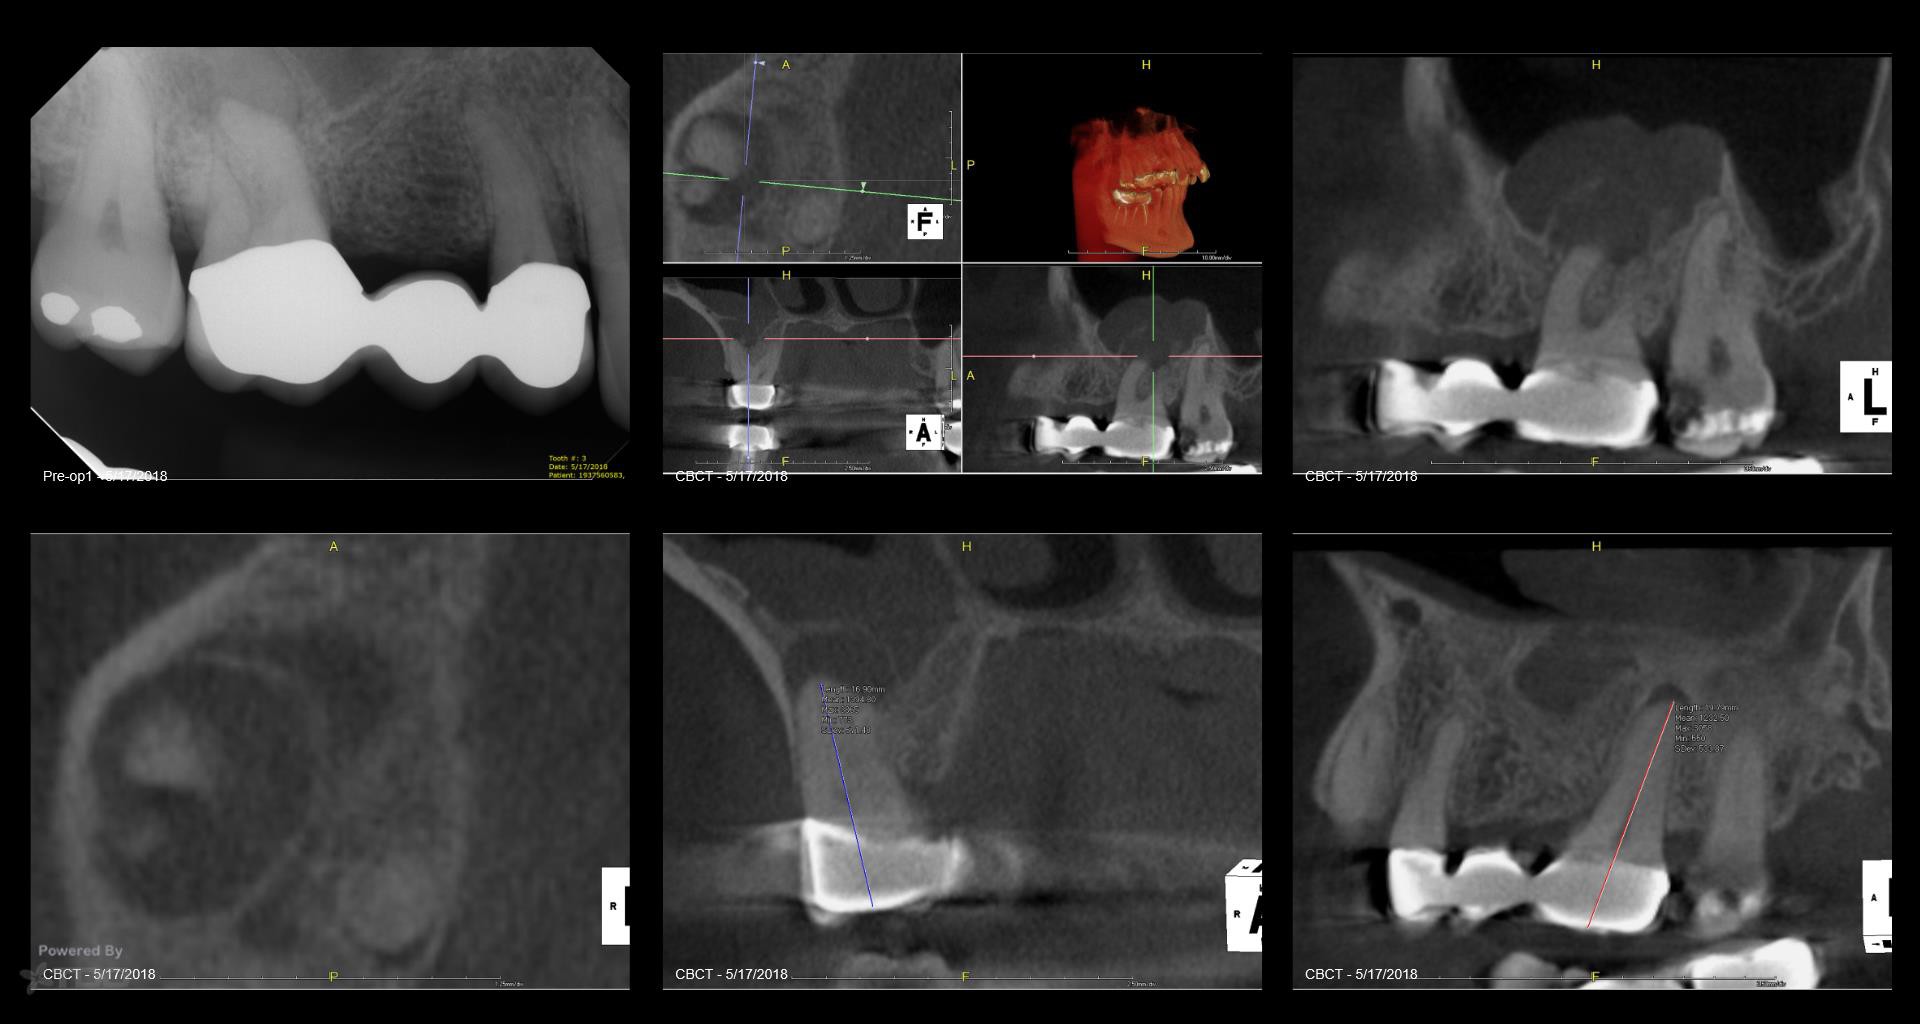

Your case sparks curiosity. With no morning consult symptoms opting for X Nav makes sense. How did the contemplation on X Nav come about and what other diagnostic strategies are you considering?

@eggy car Interesting case — X-Nav could be a solid choice here, especially if precision is a priority. Keep us posted on how it goes!